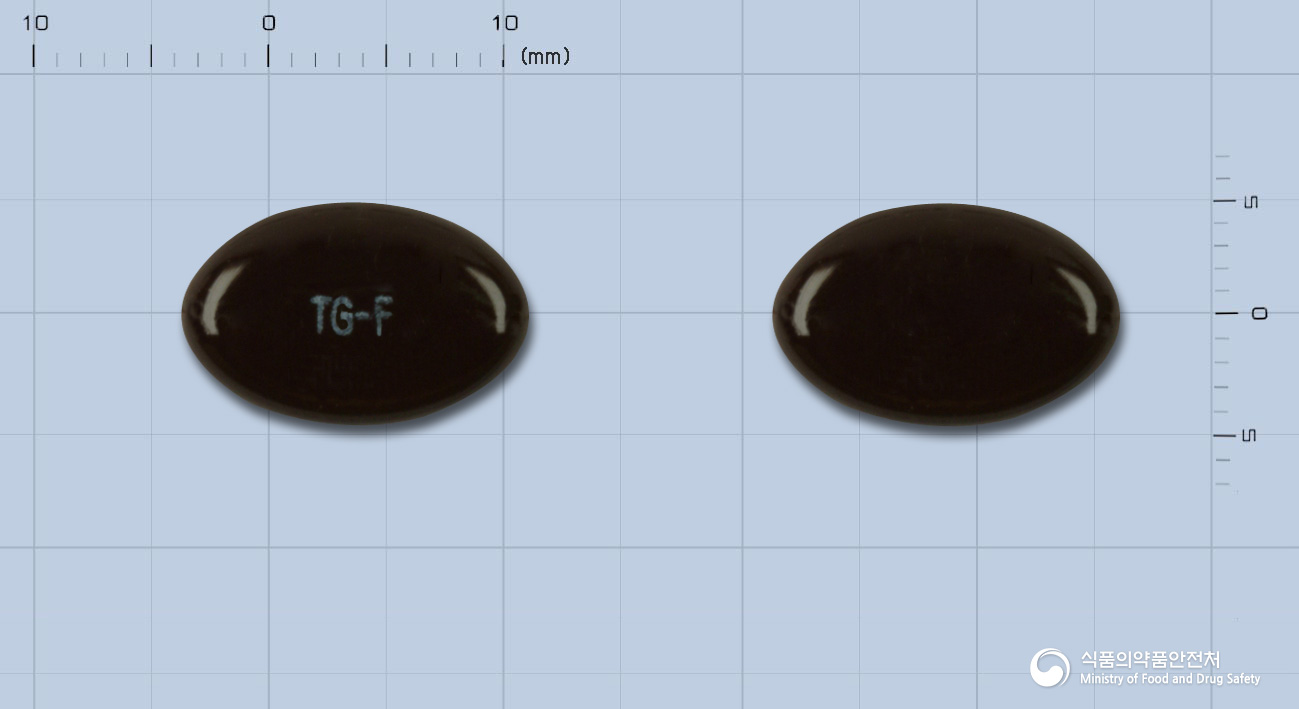

야맹증, 침침한 눈에! 타겐에프연질캡슐(빌베리건조엑스) 효능과 복용법

2. 용법·용량

- 1회 1캡슐(170 mg)씩, 1일 2~3회 식후에 복용합니다.